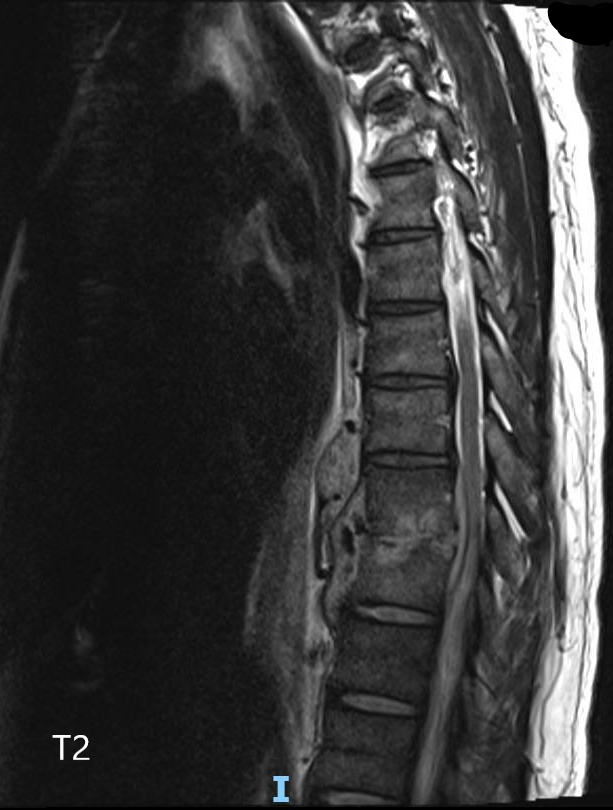

Il faut donc évoquer une pathologie rachidienne inflammatoire/infectieuse/tumorale avec syndrome de compression médullaire partiel se traduisant uniquement par une claudication médullaire : celle-ci correspond à un syndrome pyramidal, démasqué par l’effort.